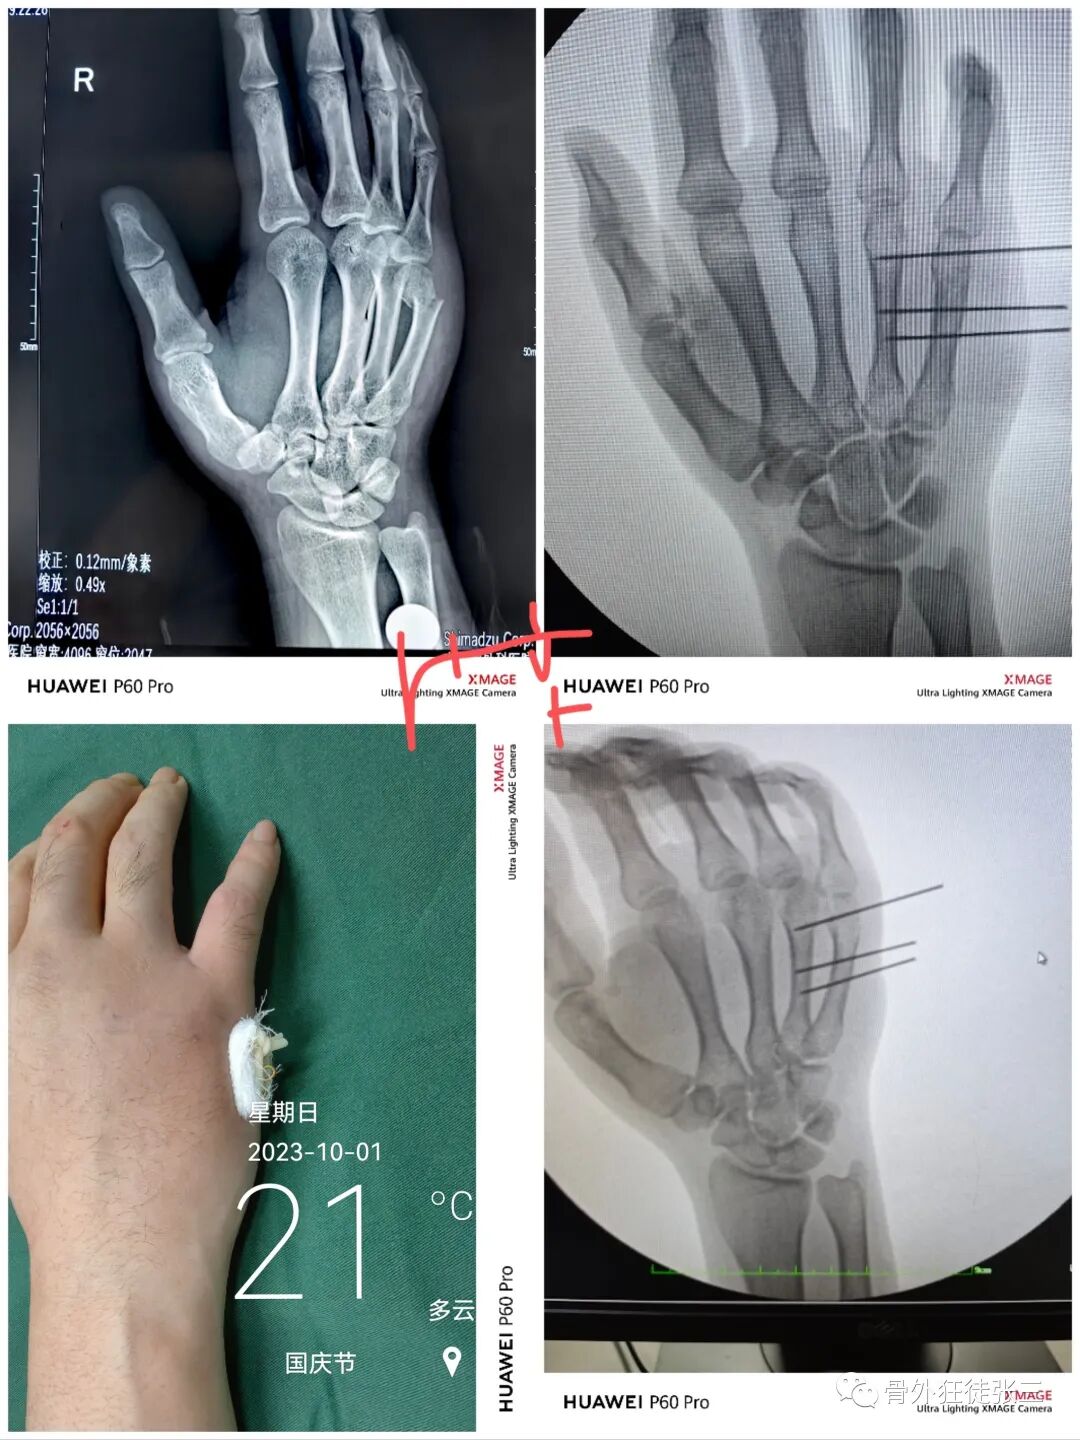

病例1,第5掌骨基底骨折,闭合复位克氏针支架,无需石膏,门诊手术,术后即刻恢复正常工作。

病例2,第4掌骨螺旋型骨折,经皮撬拔,克氏针支架。

病例5,开放性第3、4掌骨骨折,隔山打牛,克氏针支架。

病例6,开放性第2345掌骨骨折,克氏针支架

病例7,开放性掌骨,指骨骨折,克氏针内固定